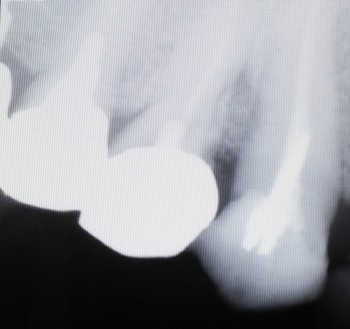

レントゲン像